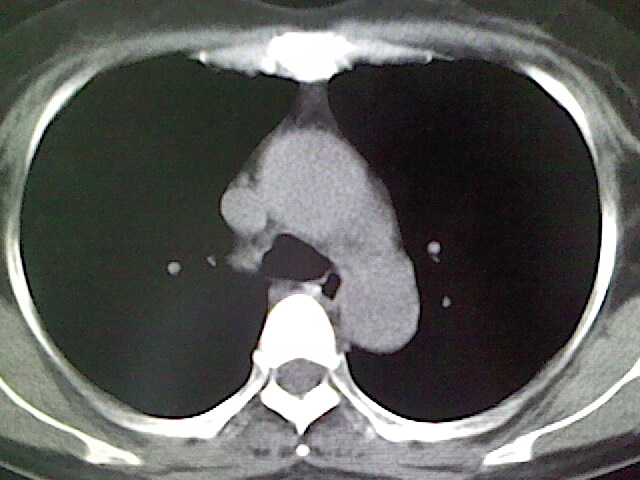

女,52岁,咳嗽,咳痰多日

左下肺陈旧纤维索条!

左肺舌段炎性改变

我见过几例,为炎症后纤维条索

慢性炎症后改变

考虑慢性炎性病灶粘连牵拉改变。

左肺舌叶纤维锁条病变。

左肺上叶下舌段炎症并局部胸膜反应。

左肺舌叶纤维索条影。

左肺舌叶段陈旧性病变

左肺舌段炎性反应。片子的质量太不好了。

左肺舌段炎性

炎性改变

左肺舌叶纤维索条影